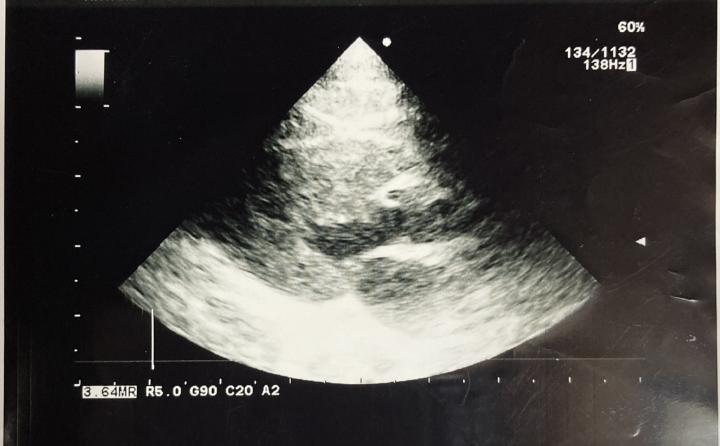

コレ、『ぼん』心臓のエコー写真です

記念にって獣医さんからもらってきました。

余っていたのかな❓